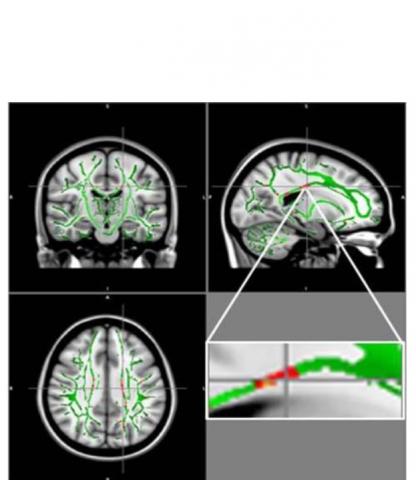

Des études de plus en plus nombreuses suggèrent que l’obésité déclenche, au-delà d’une inflammation systémique et des effets métaboliques bien connus, une inflammation du système nerveux ou neuroinflammation qui pourrait endommager des zones importantes du cerveau. Les progrès de l'IRM, dont l'imagerie en/par tenseur de diffusion permettent aujourd’hui de suivre la diffusion de l'eau le long des faisceaux de substance blanche porteurs de signaux du cerveau, ou « anisotropie fractionnelle » (FA- l’une des différentes mesures d'intégrité de la substance blanche.

Les chercheurs ont donc mesuré à l’imagerie l'anisotropie fractionnelle chez 59 adolescents obèses vs 61 témoins en bonne santé, âgés de 12 à 16 ans. C’est ainsi qu’ils ont découvert des signes de dommages (ou réduction de FA) pouvant être liés à une inflammation du cerveau des jeunes participants obèses.

Ces réductions de FA sont identifiées principalement dans le corps calleux, un faisceau de fibres nerveuses qui relie les hémisphères gauche et droit du cerveau, dans le gyrus orbitofrontal moyen, une région du cerveau impliquée dans le contrôle des émotions et dans le circuit de récompense. Aucune des zones du cerveau ne présente d’augmentation de l'anisotropie fractionnelle. « Ces changements cérébraux observés chez les adolescents obèses sont liés à des zones importantes, responsables du contrôle de l'appétit, des émotions et des fonctions cognitives », alerte Pamela Bertolazzi, chercheur en biomédecine à l'Université de São Paulo.